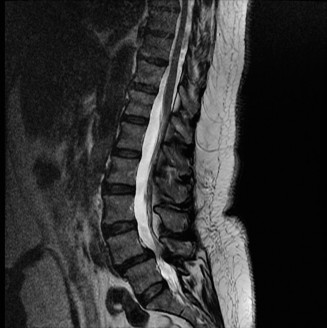

To contextualize the decision-making algorithm, consider the classic presentation of a middle-aged patient with multiple medical comorbidities. A paradigmatic case involves a 48-year-old obese female (Body Mass Index of 43) with poorly controlled diabetes mellitus who presents with severe, unrelenting low back pain, fevers, and chills. Advanced imaging, specifically magnetic resonance imaging (MRI), typically demonstrates discitis involving the L4–5 disc space with adjacent osteomyelitis of the L4 and L5 vertebral bodies. Crucially, in many early or medically responsive cases, there is an absence of epidural abscess formation, and standing radiographs reveal relatively normal sagittal and coronal alignment. When such a patient is neurologically intact—lacking saddle anesthesia, bowel/bladder incontinence, or upper motor neuron signs—the immediate clinical imperative shifts from urgent surgical decompression to aggressive pathogen identification and targeted antimicrobial therapy.

Pre-Operative Planning, Templating, and Patient Positioning

When surgical intervention becomes unavoidable, meticulous pre-operative planning is the cornerstone of a successful outcome. Advanced imaging is non-negotiable. An MRI with and without gadolinium contrast is the gold standard for defining the extent of the epidural abscess, the degree of neural compression, and the involvement of adjacent paraspinal musculature (e.g., psoas abscess). T1-weighted images typically show hypointense signals in the infected marrow, while T2-weighted and STIR sequences reveal hyperintense fluid and edema in the disc space and vertebral bodies. Gadolinium enhancement highlights the vascularized inflammatory phlegmon and the capsule of any abscesses.